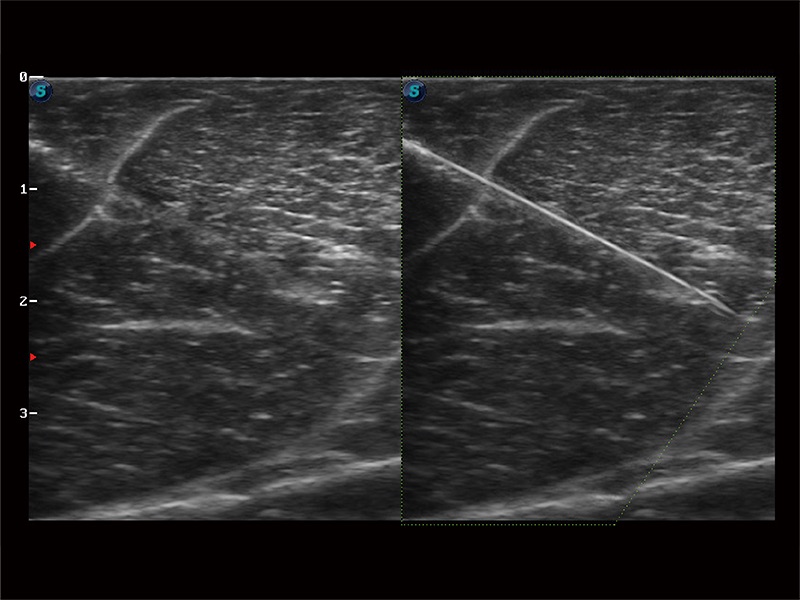

Erfasst Daten mit bis zu 3 Messlinien auf einmal, um die Wandbewegung detailliert beurteilen zu können. Verbessert die Reproduzierbarkeit und Genauigkeit der linksventrikulären Messwerte erheblich.